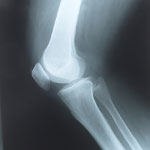

שלום רב כאבי ברכיים יכולים להיגרם מסיבות רבות, בגילאים צעירים יותר שכיח יותר תגובות דלקתיות וקרעים במניסקוס, בגילאים מבוגרים יותר שכיח יותר שחיקה של הברך. פגיעות בברך, החל משברים, קרעים במניסקוס, חבלות שונות יכולות לגרום לשחקיה מואצת של מפרק הברך, דבר היכול לבוא לידי ביטוי בקושי בטווחי תנועה של הברך, חריקות/קליקים , כאבים בקימה מישיבה או בירידת מדרגות וקושי ללכת למרחקים. הקישור הינו מאמר מפרי עטי בנוגע לשחיקת ברך www.drbender.co.il http://www.facebook.com/dr.benderbenjamin פתקים כל " בעיה בגוף" יוצרת תגובה דלקתית אשר מטרתה לנסות ולתקן את "הבעיה" בתגובה הדלקתית מפרשים חומרים אשר גורמים לכאבים NSAIDS או שמם האחר תרופות לא סטרואידליות נוגדות דלקת , גם מדכאות את הכאב בנוסף לדלקת, תרופות אלה ניתנות ללקיחה לפרק זמן קצוב NSAID's תרופות שאינן סטרואידיות הנוגדות דלקת ובכך מורידות את התגובה הדלקתית סביב מפרק הברך (ארקוקסיה,ולטרן, אטופן, ברקסין, סלקוקס) דלקות לעיתים יכולות לחלוף גם ללא עזרה תרופתית באם הבעיה שגרמה לדלקת פסקה והגוף הצליח להתגבר על הדלקת להלן רקע בנוגע לזריקות למפרק הברך הזרקות לתוך המפרק נחלקות למספר קבוצות o סטרואידים-תרופות נוגדות דלקת. זריקות סטרואידים משמשות להקלה זמנית בלבד של כאבים. (דיפורספן,דפומדרול, הידרוקורטיזון) o חומצה היאלורינית חומצה היאלורינית הינו חומר סיכה הדומה לאחד ממרכיבי נוזל המפרק. נוזל המפרק משנה את הרכבו בתהליך שחיקת המפרק, ריכוזו של החומצה ההיאלורינית במפרק יורדת בתהליך שחיקת המפרק. הזרקה למפרק הברך של חומצה היאלונירית מסייעת לשימון המפרק, מפחיתה את הכאב , מסייעת בשיפור התנועתיות ובגמישות, ותורמת לפעילות אנטי דלקתית במפרק. ישנן תכשירים המופקים מכרבולת של תרנגולת (כגון סינויסק Synvisc) וישנם תכשירים המופקים במעבדה ואינם מן החי ( ארטריז Arthease , אוסטניל Ostenil ). הסיכוי לתגובה אלרגית קטן ביותר בתכשירים אשר אינם מן החי o אורטוקין היא שיטת טיפול חדשה באוסטאוארטריטיס, הטיפול הוא טיפול ביולוגי-טבעי, מחומרים המופקים מגוף החולה עצמו. הטכנולוגיה החדשה כוללת לקיחת דם פשוטה. מהדם הנלקח מופק סרום (נסיוב) המכיל חלבונים שונים אשר מטרתם לעצור ולרפא את תהליך השחיקה. החלבונים מוזרקים למפרק. בשלבי ניסוי מצוי- הזרקה של תאי אם(גזע) STEM CELLS לברכיים , תאים אלה המחשבה היא שיכולים הם להפוך לכל תא שהוא בברכה ד"ר בנימין בנדר www.drbender.co.il http://www.facebook.com/dr.benderbenjamin

לא חייבים לחיות עם מפרקי ברך שחוקים, כואבים ומציקים. ד"ר אהרון מנחם על ניתוחים להחלפת מפרק הברך

ניתוח להחלפת מפרק הברך מאופיין באחוזי הצלחה גבוהים למדי, ומאפשר הליכה מיידית ותפקוד תקין של מפרק הברך ללא כאבים. סקירה

מיקי שלום ניתוחי החלפות מפרקים הם אופציה . ניתוחי החלפות מפרקים נעשים לשם איכות חיים ולא לשם הצלת חיים, לכן אין הכרח לעשות אותם , אלא אם החולה עצמו מציין שאיכות חייו נפגעת לרמה כזו שהוא אינו יכול לסבול את הכאבים ואת ההגבלה בתפקוד המפרק . בצילומים ובבדיקה ניתן להתרשם מה מידת השחיקה של המפרק ועד כמה תפקוד המפרק נפגע ניתוחי החלפות מפרקים נעשים קודם כל עקב כאבים והגבלה בתפקוד המפרק. מטרתו של הניתוח הינו שיפור בכאבים ובתפקוד המפרק באם הטיפול הלא ניתוחי אינו עוזר ואיכות החיים נפגעת ניתן לשקול ניתוח ישנם זריקות לברך המופקות מכרבולת של תרנגולת, וישנן זריקות לברך המופקות במעבדה, ישנן זריקות הנתונות שלוש פעמים וישנן הנתונות חמש פעמים(אורטוקין) וישנן הניתנות פעם אחת . ישנן זריקות בתוספת חומרים כגון מניטול להלן רקע בנוגע לזריקות למפרק הזרקות לתוך המפרק נחלקות למספר קבוצות o סטרואידים-תרופות נוגדות דלקת. זריקות סטרואידים משמשות להקלה זמנית בלבד של כאבים. (דיפורספן,דפומדרול, הידרוקורטיזון) o חומצה היאלורינית חומצה היאלורינית הינו חומר סיכה הדומה לאחד ממרכיבי נוזל המפרק. נוזל המפרק משנה את הרכבו בתהליך שחיקת המפרק, ריכוזו של החומצה ההיאלורינית במפרק יורדת בתהליך שחיקת המפרק. הזרקה למפרק הברך של חומצה היאלונירית מסייעת לשימון המפרק, מפחיתה את הכאב , מסייעת בשיפור התנועתיות ובגמישות, ותורמת לפעילות אנטי דלקתית במפרק. ישנן תכשירים המופקים מכרבולת של תרנגולת (כגון סינויסק Synvisc) וישנם תכשירים המופקים במעבדה ואינם מן החי ( ארטריז Arthease , אוסטניל Ostenil ). הסיכוי לתגובה אלרגית קטן ביותר בתכשירים אשר אינם מן החי o אורטוקין היא שיטת טיפול חדשה באוסטאוארטריטיס, הטיפול הוא טיפול ביולוגי-טבעי, מחומרים המופקים מגוף החולה עצמו. הטכנולוגיה החדשה כוללת לקיחת דם פשוטה. מהדם הנלקח מופק סרום (נסיוב) המכיל חלבונים שונים אשר מטרתם לעצור ולרפא את תהליך השחיקה. החלבונים מוזרקים למפרק. אחוזי הצלחה של זריקות מסוימות תלוי בגורמים רבים ביניהם שלב המחלה , ככל שהשחיקה גדולה יותר הסיכוי שהזריקות יעזרו הוא קטן יותר. באם הזריקות עוזרות ניתן לחזור עליהן , חומצה היאלורינית ניתן לחזור כל חצי שנה עד שנה http://www.drbender.co.il/faq?fb_comment_id=fbc_10150473688962175_20083748_10150474673827175#f2e4ba8a2e539ba ניתן להתעדכן במאמר על שחיקה של הברך בקישורים הבאים www.facebook.com/drbenderbenjamin http://www.drbender.co.il/articles בברכה ד"ר בנימין בנדר